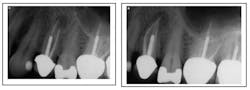

Missed canal anatomy cases ...

Missed MB2 canal

Missed third canal in upper first premolar

Separated instrument with incomplete fill and debridement